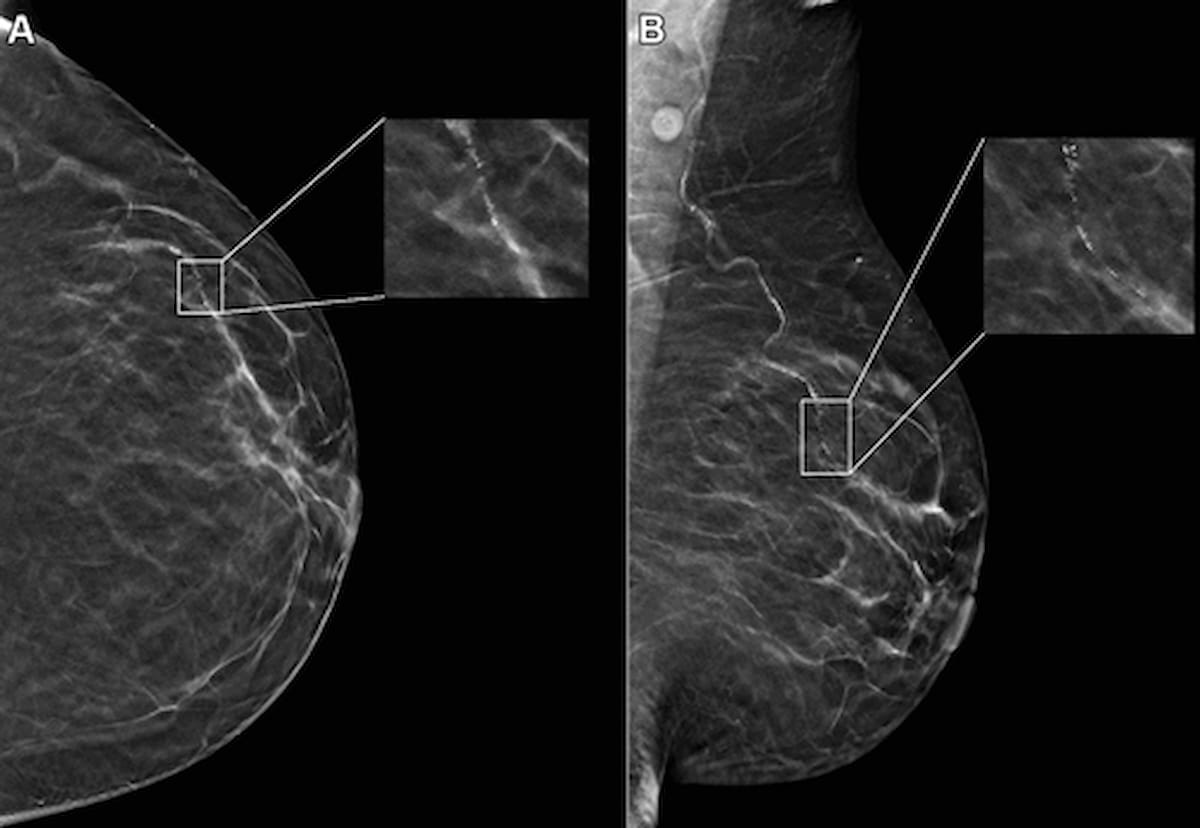

An emerging deep learning algorithm had a lower AUC and sensitivity than urological radiologists for differentiating between small renal masses on computed tomography (CT) scans but had a 21 percent higher sensitivity rate than non-urological radiologists, according to new research.